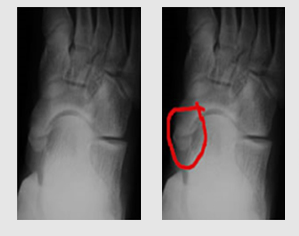

인구의 10% 정도만 생기지만 어미 뼈와 새끼 뼈가 잘 붙어있으면 모르고 지낸다. 하지만 성장 시기인 청소년기에 발을 삐거나 과격한 운동을 하여 당하는 부상으로 두 뼈가 어긋나면 문제가 발생한다. 어긋난 두 뼈가 부딪혀 통증과 염증을 일으킨다.

주상골은 쿠션 역할을 하는 발아치의 천장 역할을 한다. 인대가 이를 잡아주어 높게 유지되나 인대가 부주상골에도 붙어버리면 힘이 약해서 주상골이 내려앉는다. 이를 방치할 경우 아치가 내려앉아 평발이 될 수 있다.